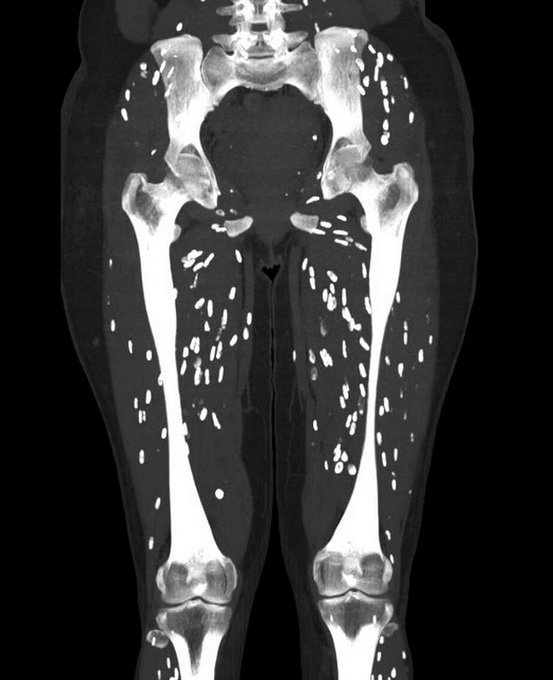

Q: Young male with bone pain and anaemia. What's the diagnosis? ANSWER: https://t.co/3vKZ8AL680 #FOAMrad #FOAMed